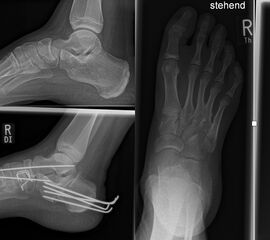

Zusätzlich schränken Wachstumsfugen die Wahl der Osteosynthese ein. Eine die Fuge kreuzende Osteosynthese ist ausschließlich mit Kirschner-Drähten möglich (Abb. 3).

Abb. 3 a-j: Beispiel einer Calcaneusverschiebeosteotomie mit offenen Wachstumsfugen und der entsprechenden Osteosynthese mit Kirschner Drähten. Lokalisation der Osteotomie (a), Lage der Fräse (b-d), Drahtlage mehrere Ansichten (e-h), Heilung der Osteotomie 4 Wochen postoperativ und Entfernung der Drähte (i-j).